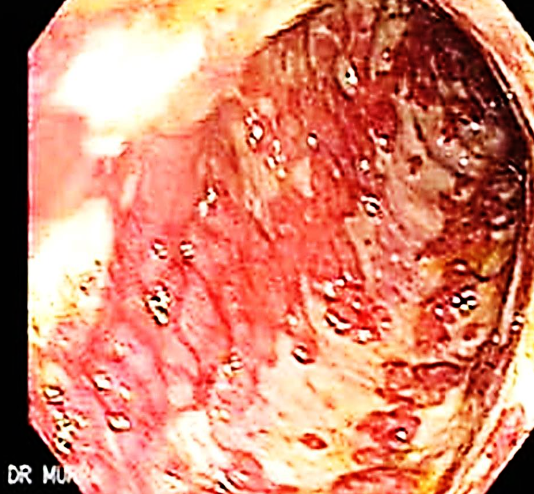

Case 6

This is an endoscopic image of colon affected by ulcerative colitis. The mucosa is blotchy and broken in many places.

Q1: Name 3 common clinical symptoms of ulcerative colitis?

Lower abdominal pain, diarrhea, blood and mucus with the stool.

Q2: Name 2 features of a severe episode of UC?

Leukocytosis, increase frequency of the stool more than 6 times in the day, anemia.

Q3: Name 2 ttt options for UC?

5-ASA, Corticosteroids.

Q4: Name 3 extracolonic manifestations of UC?

Arthritis, Ancylosing spondylitis, Uveitis, Episcleritis